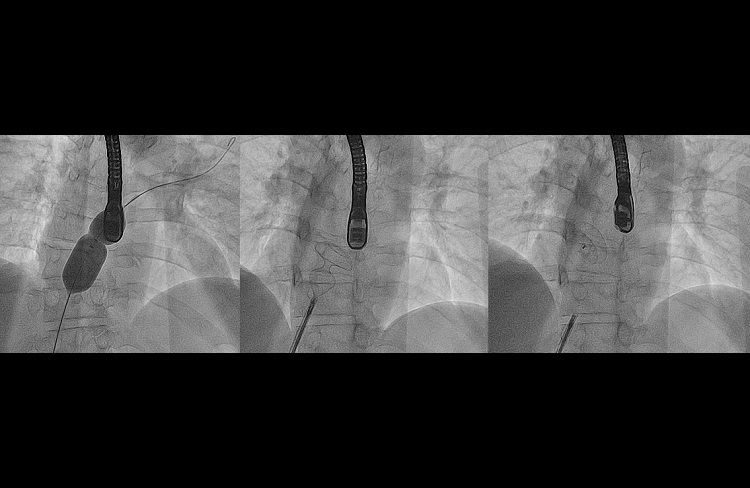

- ostrą zatorowością płucną – Klinika specjalizuje się w leczeniu chorych z ostrą zatorowością płucną. W OIOK Kliniki pacjenci są kwalifikowani do leczenia interwencyjnego w ramach PERT (Pulmonary Embolism Response Team) w tym do pilnych embolektomii przezskórnych w ramach 24 godzinnego dyżuru;

Dzięki wykwalifikowanemu personelowi jesteśmy liderami na skale europejską w leczeniu przezskórnym ostrej zatorowości płucnej (pracownia wyposażona jest w system do trombektomii reolitycznej AngioJet, Boston Scientific oraz trombektomii aspiracyjnej – Penumbra Indigo) oraz przewlekłego zakrzepowo-zatorowego nadciśnienia płucnego (CTEPH).

- przezskórna embolektomia tętnic płucnych z wykorzystaniem nowoczesnego systemu do trombektomii mechaniczno-reolitycznej Angiojet oraz cewników do trombektomii apiracyjnej PENUMBRA Indigo;